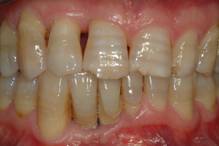

Fig 9

Clinical re-evaluation 10 days after surgery

Fig 10

Clinical re-evaluation 6 months after surgery

The management of the soft tissues was easy and healing almost in a high rate occurred after the first treatment. During sutures removal, no important tissues inflammations were observed. At a 10-day follow-up, post-operative clinical assessment demonstrated a gingivitis grade of 0 or 1. Thanks to the bacteriostatic properties of the tested polymer, a more effective control of the surgical wound no bacterial contamination of the surgical site was observable in all instances [fig. 9]. Post-operative radiographs showed absence of bone remodelling, and satisfactory filling of the infra-bone defects with the graft material in situ. After 6 months, radiographs showed presence of mild bone remodelling and excellent infra-bone filling [fig. 10-11].